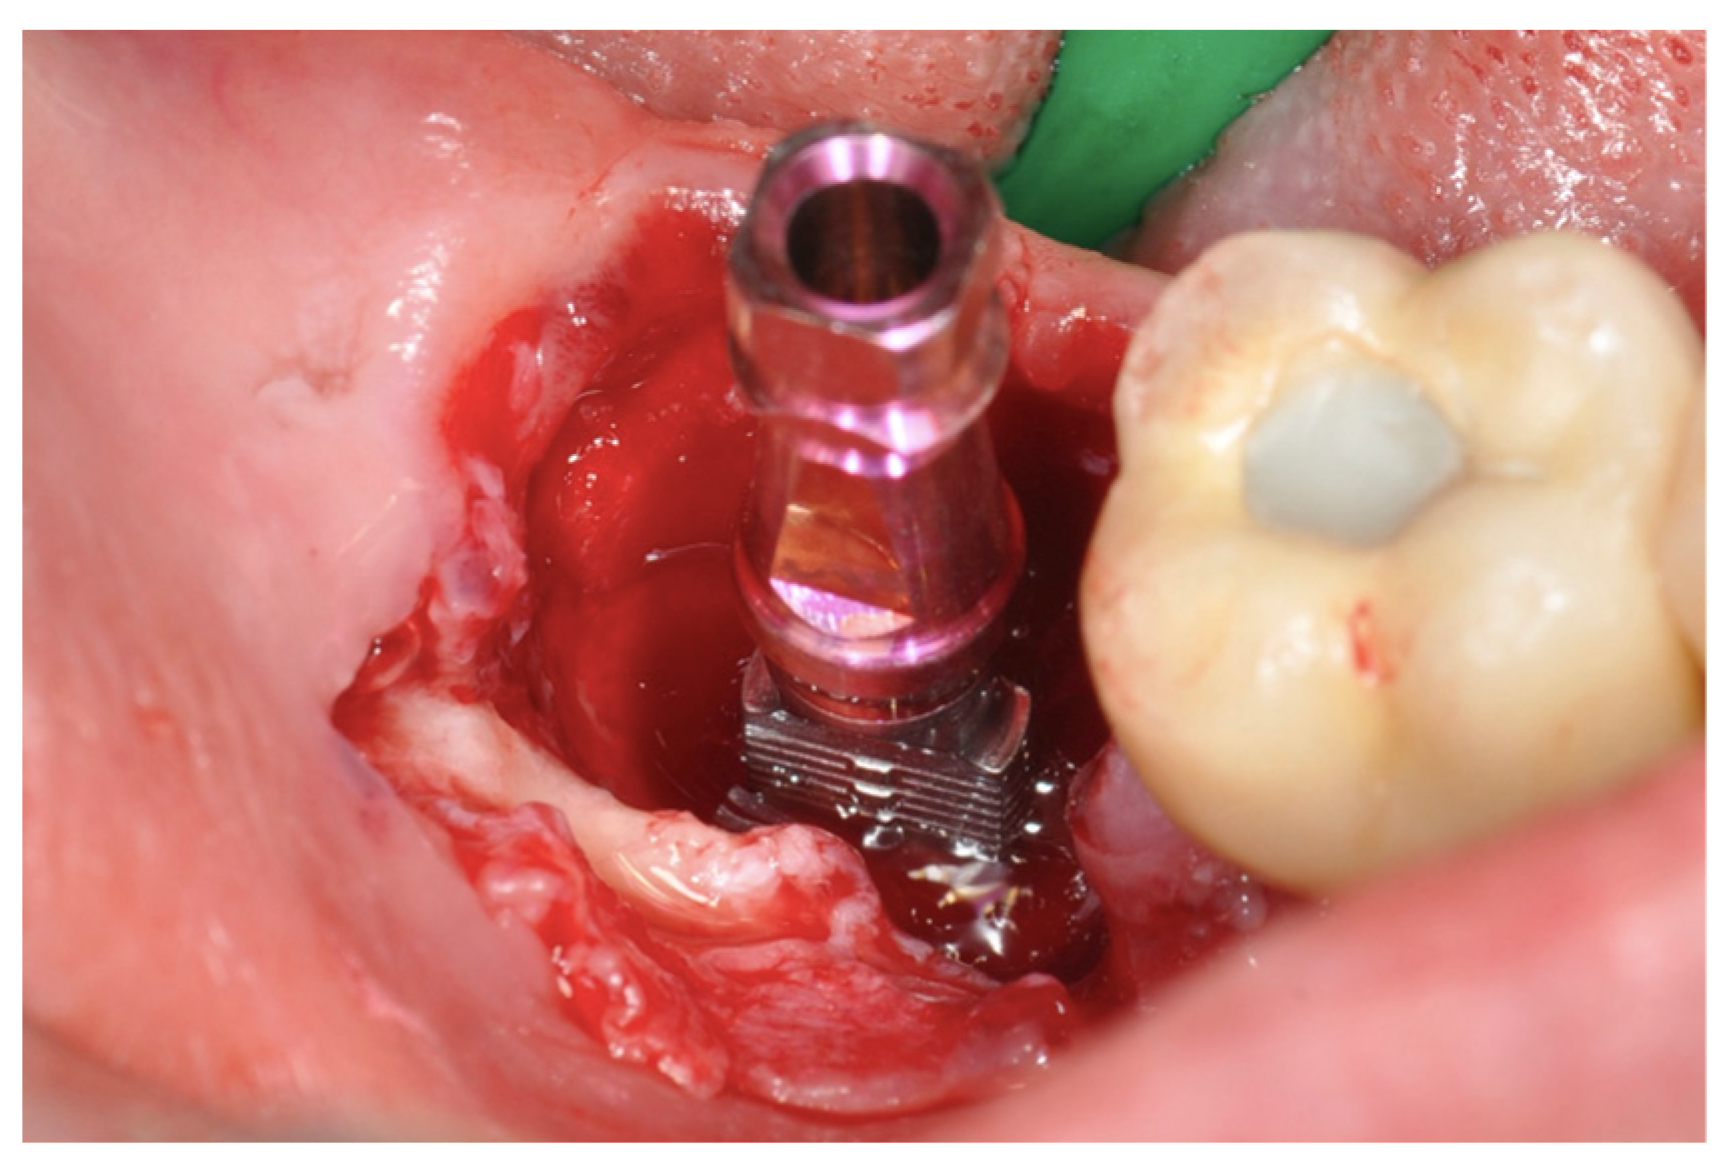

2.2. Surgical Technique